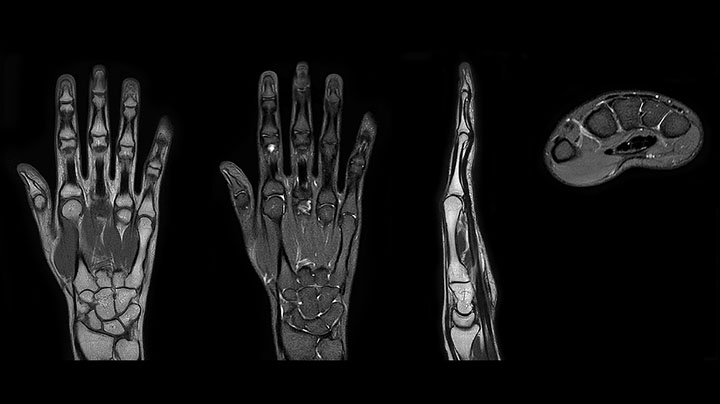

Prodiva imaging of the hand covers the fingertips and includes the full wrist as well. The dS MSK M coil is easy to use.

MRI of the finger with high SNR and good resolution in a 10 cm field of view on Prodiva 1.5T. The diagnosis in this 63-year-old patient is bone elasmanosis.